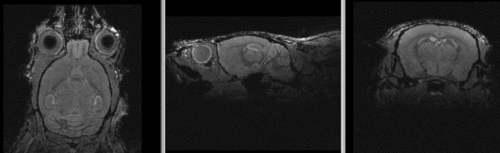

shown are, from left to right, panels of axial, sagittal and coronal views.

original unregistered brains original, not registered

affine registered brains affine registered

registered brains after 5x5x5 nonrigid BSpline alignment registered brains after 5x5x5 nonrigid BSpline alignment